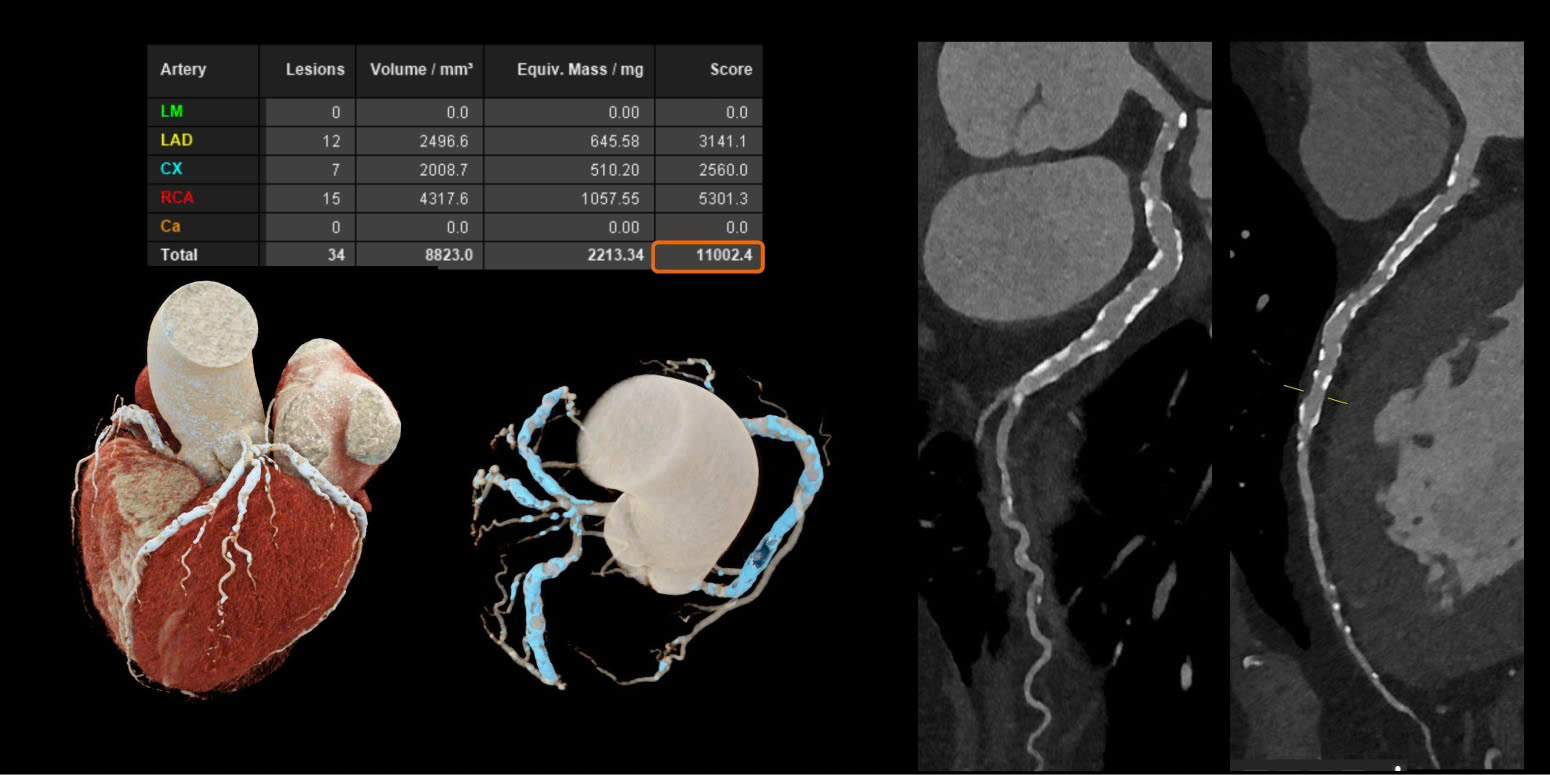

Đặc biệt trong lĩnh vực tim mạch, với những bệnh nhân đã đặt stent hoặc có tình trạng vôi hóa mạch vành nặng – vốn là những trường hợp khó đánh giá bằng CT thông thường – công nghệ này cho thấy ưu thế vượt trội. Hình ảnh thu được rõ nét hơn đáng kể, giúp bác sĩ quan sát chính xác lòng mạch và các mảng xơ vữa.

Đáng chú ý, ngay cả khi bệnh nhân có nhịp tim cao hoặc loạn nhịp, việc chụp vẫn đảm bảo chất lượng mà không cần sử dụng thêm thuốc hỗ trợ, mở ra nhiều tiềm năng cải thiện hiệu quả chẩn đoán và điều trị trong tương lai.

Trong ung thư, việc phát hiện sớm những tổn thương rất nhỏ luôn đóng vai trò quyết định đến hiệu quả điều trị. Với công nghệ cắt lớp vi tính lượng tử, hình ảnh có thể được tái tạo với lát cắt siêu mỏng chỉ tới 0,2 mm – một bước tiến đáng kể so với trước đây.

Nhờ độ phân giải vượt trội này, nhiều bất thường nhỏ vốn dễ bị bỏ sót nay có thể được nhận diện rõ ràng hơn. Điều này giúp bác sĩ không chỉ phát hiện sớm mà còn đánh giá chính xác hơn đặc tính của tổn thương, từ đó hỗ trợ hiệu quả trong chẩn đoán và theo dõi nguy cơ tái phát.